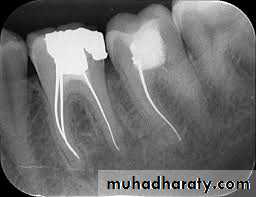

Canals filled to the apical dentinocemental junctionThey are filled to the anatomic limit of the canal